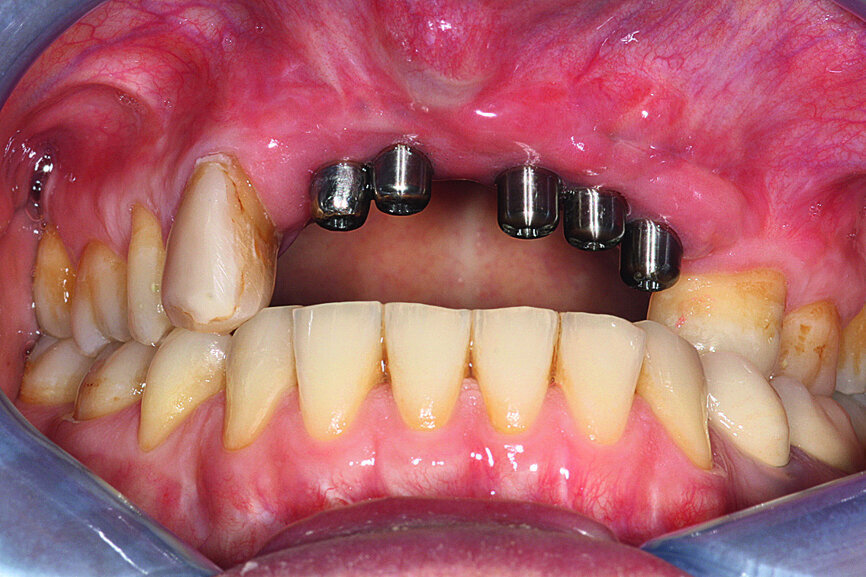

Fig. 36: Installation of the final prosthesis and verification of

correct occlusion. Screw channels filled with composite.

Fig. 37: Installation of the final prosthesis and verification of